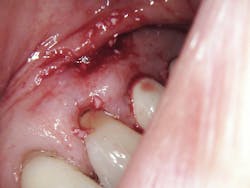

Continuing to adjust spot size, mist, and power as necessary, the laser was used to enlarge the fenestration in the buccal plate (figure 4). The granulation tissue from the abscess then had to be removed in order to expose the root for amputation. Simultaneously, a slot prep was cut for retrograde bioceramic restoration (figure 5).